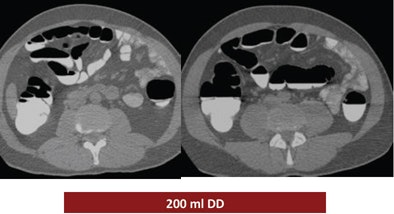

The study looked at three groups of 30 patients who underwent virtual colonoscopy after a same-day bowel preparation. Group 1 ingested 200 mL of undiluted DD the day of the exam, group 2 drank 100 mL of the agent the day of the exam, and group 3 ingested a low-dose polyethylene glycol (PEG) formula (macrogol) the two days before the exam, followed by 100 mL of DD the day of the exam.

According to the results, the mean segment quality values were 2.8 in patient group 1, 2.6 in group 2, and 3.2 in group 3.

"We had the best results in group 1, group 3 had the medium result, and group 2 had the worst results," he said. "The main difference was in the cecum," which produced a mean quality score of 2.3 for group 1, 1.6 for group 2, and 3 for group 3.

| Judged subjectively, the best overall prep quality was found in group 1, followed by group 3, with the worst results in group 2. By segment, the largest differences in quality were found in the cecum, with mean quality scores of 2.3 for group 1, 1.6 for group 2, and 3 for group 3. All images courtesy of Dr. Riccardo Ferrari. |

Group 1 had the best-quality results, with well-marked colonic mucosa but significant residual fluid. The use of 100 mL DD combined with low-dose polyethylene glycol over two days may have improved fecal tagging by softening the stool before the ingestion of the iodinated agent. In addition, no side effects were reported among the patients who ingested the PEG preparation for two days before the exam (group 3), Ferrari said.

| Above, the use of 200 mL DD in group 1 yielded the highest quality scores. While the colonic mucosa was well marked, significant volumes of fluid remained in the colon, similar to the 100 mL DD preparation (group 2, below). The use of 100 mL combined with low-dose polyethylene glycol over two days (bottom image) may have improved fecal tagging by softening the stool before the ingestion of DD. |